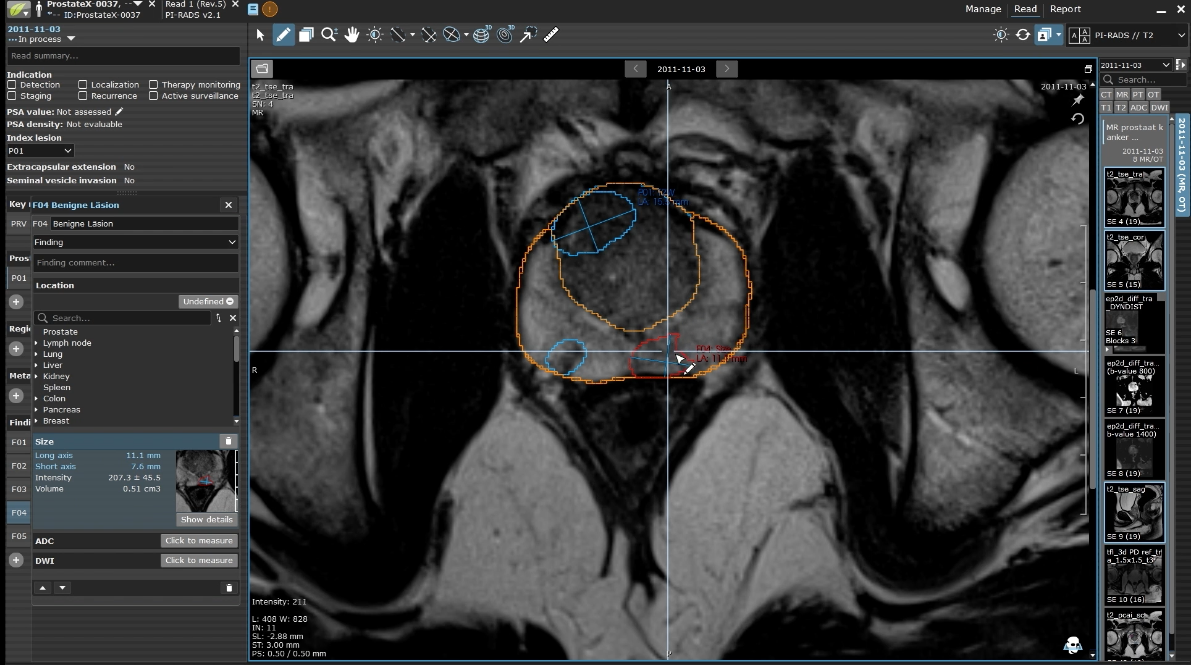

Example of combined product features of Prostate.Carcinoma.ai plug-in in Lesion™ software

Fast focus to regions of interests (ROI)

Prostate.Carcinoma.ai automatically segments the prostate, its zones, and conspicuous lesions on all T2w images. A clinical study has shown that this analysis time is reduced by approximately 30%.

Example of combined product features of Prostate.Carcinoma.ai plug-in in LesionTM software

Facilitated volumetry

Achieving more accurate calculations of prostate volume and PSA density may contribute to improving urologists' TRUS-guided biopsies with better treatment options.

Manual adaption is possible

Radiologists can make manual adjustments directly in the diagnostic software if needed (adapt or delete). Volumes and coordinates are then recalculated automatically.